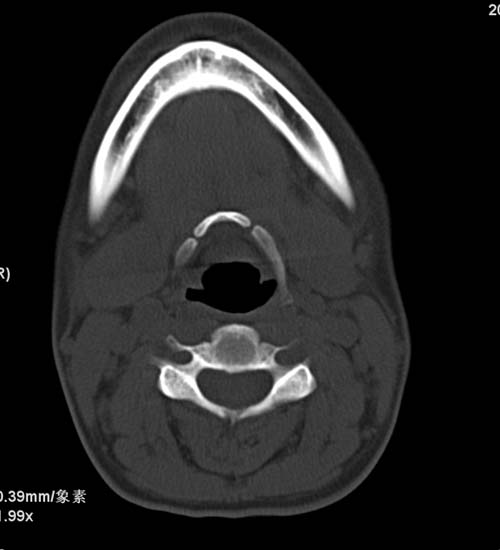

标题: CT22662:女 23 自述双侧颌下腺肿大年余 近来疼痛 左侧明显 [打印本页]

标题: CT22662:女 23 自述双侧颌下腺肿大年余 近来疼痛 左侧明显

见双侧颌下腺略肿大  未见结石及钙化 考虑双侧慢性炎症 ?请指教